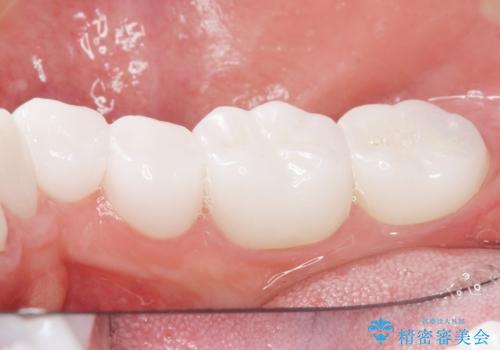

クラウンの色味・形態の修正や患者様のお仕事のご都合で来院できない期間があったことにより、予想より治療期間が長くなってしまいましたが、審美的な仕上がりにご満足頂けました。

クラウンの色味に関して、自然な白さ(シェードA1~NW0.5)のクラウンを作製・試適したところ「もっと白くしたい」と希望され、当院で最も明度の高い色(シェードNW0)に修正しました。

被せ物の種類:オールセラミッククラウン スタンダード (シェード:NW0)